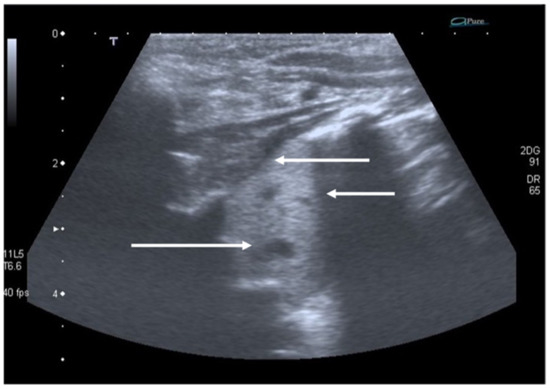

In bronchiolitis, the main ultrasound findings are: areas of subpleural consolidations defined as hypoechogenic areas with parenchymatous appearance and irregular margins, the presence of coalescent B-lines (three or more B-lines in each intercostal space) up to the “white lung” or focal presence of multiple B-lines (one or two B-lines in each intercostal space) and abnormalities of the pleural line (Figure 8 and Figure 9) [47]. Several studies demonstrated that lung ultrasound findings strictly correlate with the clinical evaluations in infants with bronchiolitis [48,49], and the 2020 consensus established LUS as a useful tool in assessing the severity of the disease [37]. Therefore, LUS could be used as support of the clinical examination in the identification of infants who may require more intensive care as supplementary oxygen or respiratory support [36].

Figure 8.

Bronchiolitis. Coalescent B-lines arising from the pleural line.

Figure 9.

Bronchiolitis. Subpleural consolidation (white arrow).